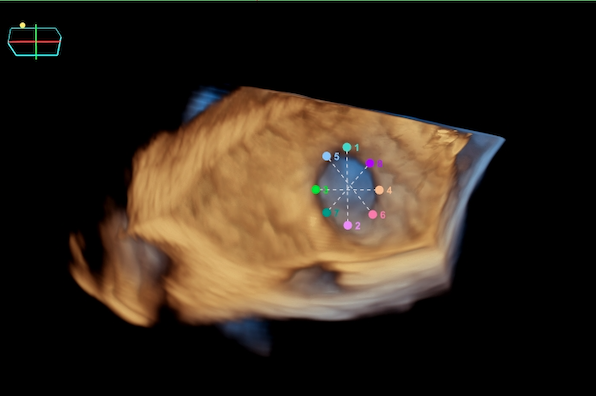

In this case, an elderly female with persistent atrial fibrillation and elevated stroke risk presented for left atrial appendage occlusion (LAAO) evaluation. Due to geographic and logistical challenges in accessing TEE under sedation, the care team opted for a 4D ICE-guided (AcuNav Lumos, Siemens Healthineers) LAAO procedure performed with conscious sedation. Multiplanar reconstructions (MPRs) from 4D ICE were used to assess the LAA’s landing zone dimensions, enabling precise device sizing (Figure 1).